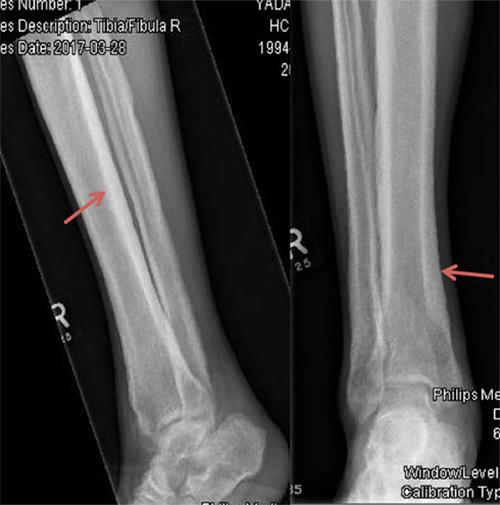

We described the case of a 23-year-old Nepalese man with seropositive rheumatoid arthritis and abnormal x-ray findings, found to be due to a very rare bone disease: Camurati Engelmann disease or progressive diaphyseal dysplasia (PDD). This is the first case reported in the Gulf area, although approximately 300 cases have been described worldwide. These patients usually present with limb pain and easy fatigability. Our patient first presented with bilateral, symmetrical inflammatory polyarthritis involving the knees, ankles and wrists but sparing the hands and feet. The diagnosis of PDD in our case was based on the classic radiological findings and a bone scan.

我们描述了一名23岁尼泊尔男性的病例,他患有血清阳性类风湿关节炎且X线检查结果异常,后来发现是由一种非常罕见的骨病引起的:卡穆拉蒂-恩格尔曼病或进行性骨干发育异常(PDD)。这是海湾地区报道的首例病例,尽管全球已描述了约300例。这些患者通常表现为肢体疼痛和易疲劳。我们的患者最初表现为累及双膝、双踝和双腕的双侧对称性炎性多关节炎,但手部和足部未受累。我们病例中PDD的诊断基于典型的放射学表现和骨扫描。